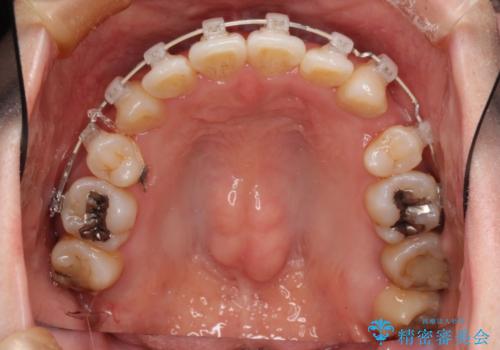

初診時の歯並びの状態としては、上下に強いガタガタがある状態であり、それが原因で口腔内の清掃状態も極めて悪い状況でした。

スペースの不足量が著しく、上下左右の抜歯を伴うワイヤー矯正にて治療を行いました。

抜歯によるスペースを利用し、強いがたつきの改善を行いました。

- 審美装置(ブラケット:白/ワイヤー:白)